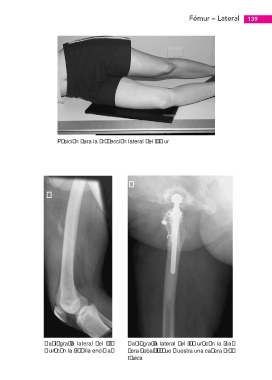

Posición para la proyección lateral del fémur

Radiografía lateral del fé-   Radiografía lateral del fémur, con la “ca-

mur, con la “rodilla encima”  dera debajo”, que muestra una cadera pro-

tésica